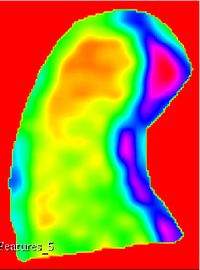

This extensions contain several modules that can be used to compute feature maps of N-Dimensional images using two well-known texture analysis methods: the study of Grey Level Co-occurrence Matrix (GLCM) and the study of Grey Level Run Length Matrix (GLRLM). The main algorithms used in this extension are part of a remote module of ITK called itkTextureFeatures Key Features:

Texture features

Texture feature maps

Co-occurrence texture feature maps